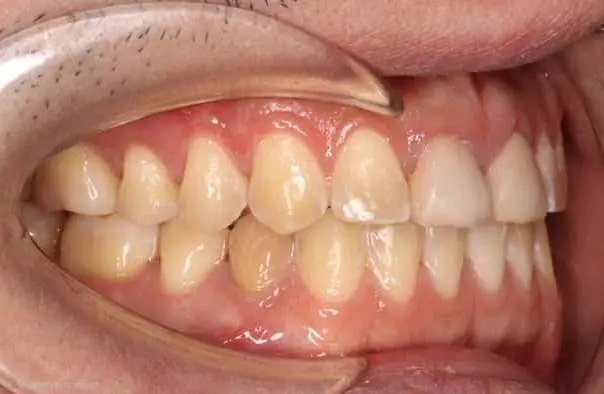

Crowding

Before